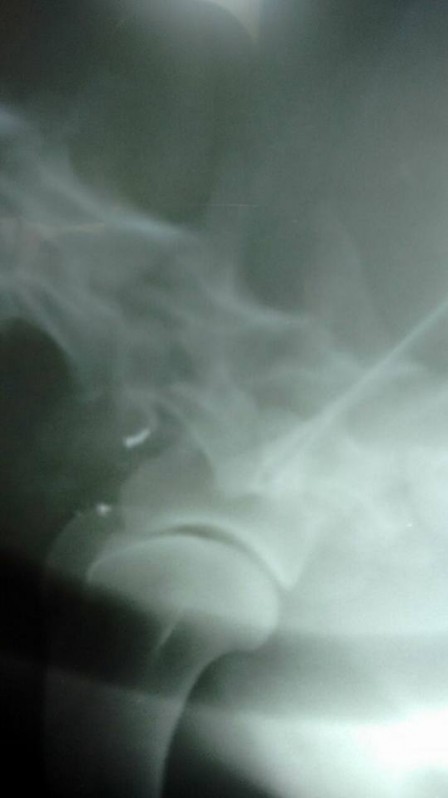

O proprietário então trouxe o animal para ser examinado pelo Médico Veterinário da Clínica Mundo Animal, de Osvaldo Cruz, o experiente Dr. Osvaldo Ponteli, que rapidamente diagnosticou que o ferimento tinha sido provocado por um disparo de arma de fogo e quer o projétil estava alojado na musculatura do cachorro.

Segundo o Veterinário, o projétil é de pequeno calibre, provavelmente um chumbo de espingarda ou se trata de um projétil de calibre 22, porém, se fragmentou com o impacto e continua alojado na paleta do Cão.

O animal passa bem, não corre risco de morte, está se recuperando e ainda será decidido se o projétil será retirado ou se poderá permanecer no local, uma vez que não representa risco à saúde do animal, que permanece internado sob cuidados, na Clínica Mundo Animal de Osvaldo Cruz, que fez uma postagem em uma rede social, mostrando o animal sendo tratado.